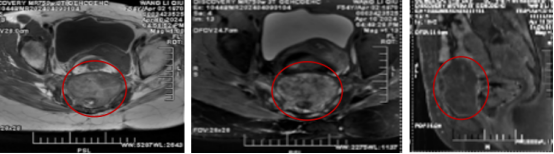

治疗后1年肿瘤7.8×7.4cm,左图为MRI的T1轴位,中图为T2轴位,右图为T1矢状位位

治疗后2年肿瘤7.5×5.3cm,MRI:T2轴位 T2矢状位

治疗后三年,肿瘤继续吸收变小了,患者的二便功能和运动运动恢复的很不错,疼痛于治疗后一年后明显缓解并缓慢悄失。